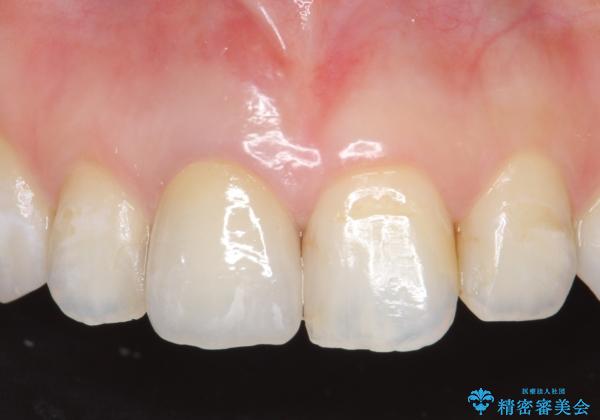

- 右上1番目の歯の変色が気になると来院された方の症例です。

検査の結果、右上1の歯は失活(歯の神経が死んでいること)していたため根管治療を行いました。

その後オールセラミッククラウン(スペシャル)による補綴を行いました。

なお隣在歯の樹脂は今後治療していく予定です。